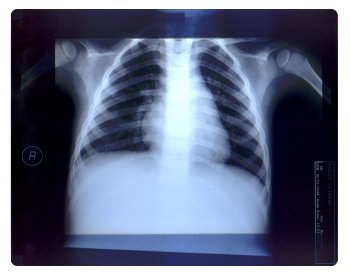

Röntgen filmleri hem görülebilir ışığa hem de x-ışınına duyarlıdır. Ekspojür olduğunda emülsiyon etkilenir. Gözle görülmeyen latent görüntü oluşur (Latent dönem). Banyo işlemi ile görüntü manifest hale gelir (Manifest görüntü dönemi).

Işık alan kesimler siyah, diğer kesimler beyaz görülür. Değişik ekspojür değerlerinde değişik dansite oluşur. Filmin ekspojüre verdiği değere bakarak, filmin kontrast ve hızını belirleyebiliriz. Dansitometre ile ölçülür. İşleme sensitometri adı verilir.